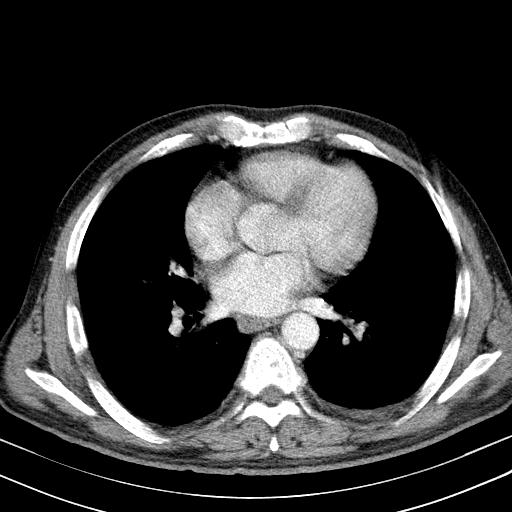

先行ct平扫,纵膈内多发软组织影,ct值约为36hu,以下为增强扫描和腹部平扫。

经典?纵膈多发肿大淋巴结。腹膜后未见异常。

淋巴瘤?胸腺瘤?

支持淋巴瘤

淋巴瘤可能

1)考虑淋巴瘤。2)双侧少量胸腔积液。